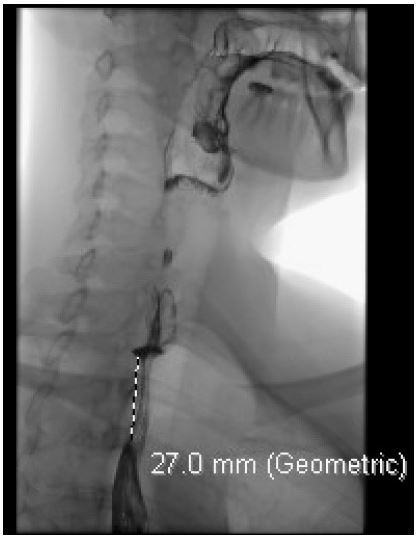

A 39-year-old female with a past medical history of chronic bronchitis presented for evaluation of progressive dysphagia. She reported a long-standing history of difficulty swallowing, often experiencing transient substernal obstruction of solid food and occasionally liquids. Her symptoms subsequently progressed until she was tolerating only minimal oral intake accompanied by unintentional weight loss, prompting her to seek care. A barium esophagram revealed a 2.7 cm extrinsic compression in the upper esophagus. A CT angiogram of the chest identified an aberrant right subclavian artery compressing the esophagus. An Esophagogastroduodenoscopy (EGD) confirmed extrinsic compression in the upper third of the esophagus, consistent with suspected dysphagia lusoria. Esophageal biopsy showed normal mucosa. She underwent right subclavian to carotid transposition and Thoracic Aneurysm Endovascular Repair (TAVER). At a follow-up assessment two weeks postoperatively, she reported complete resolution of dysphagia.

Figure 1: Barium swallow showing approximately 2.7 cm length of extrinsic compression of the upper esophagus resulting in moderate retention of the ingested bolus.